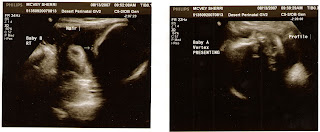

The monitoring appointments take 2 to 3 hours each and they listen to each heartbeat and monitor for contractions. It also takes a long time because my specialist’s office doesn’t have a triplet monitor, only for twins. Then the doctor does an ultrasound scan to ensure each baby is moving. Sometimes they are stubborn. Baby A doesn’t move much and hangs out really low by my pelvic bone, baby B flops like a fish between the middle and the right side and Baby C moves around some and hangs out very high almost in my chest, which makes it difficult at times to breath deeply. So we are now in a holding pattern. Holding for whatever comes next. We will keep everyone posted as to what is going on as soon as more news is available.